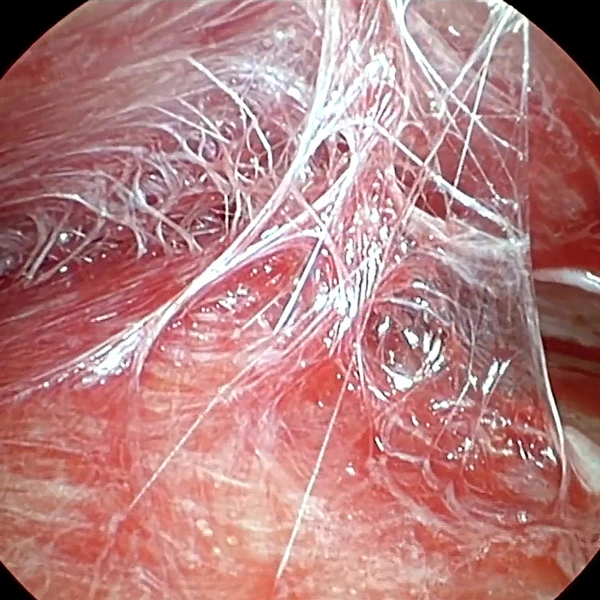

Второе пространство – межфасциальное. Оно находится между темпоропариетальной фасцией (Слой 3) и поверхностным листком собственной височной фасции (Слой 4) (Рис. 3). Это самый безопасный слой, который представлен рыхлыми волокнами соединительной ткани. Их называют «волосы ангела» (Рис. 4).

Височный лифтинг филлерами Neauvia

Рисунок 3

Рисунок 4